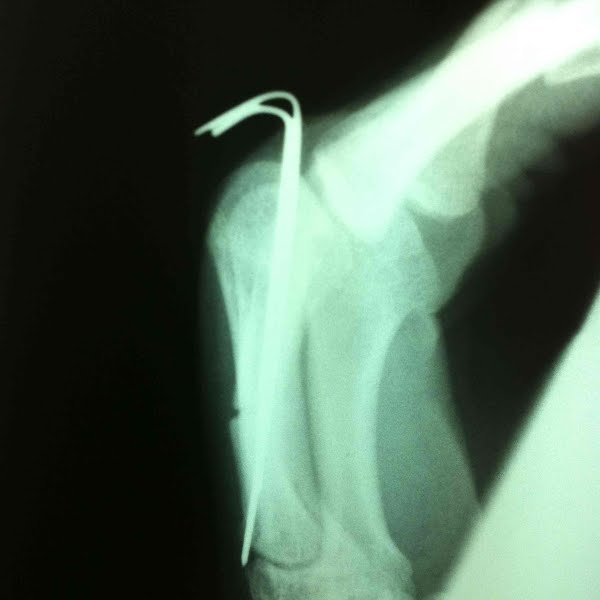

5th metacarpal fracture

when life breaks you, come back stronger as wolverine